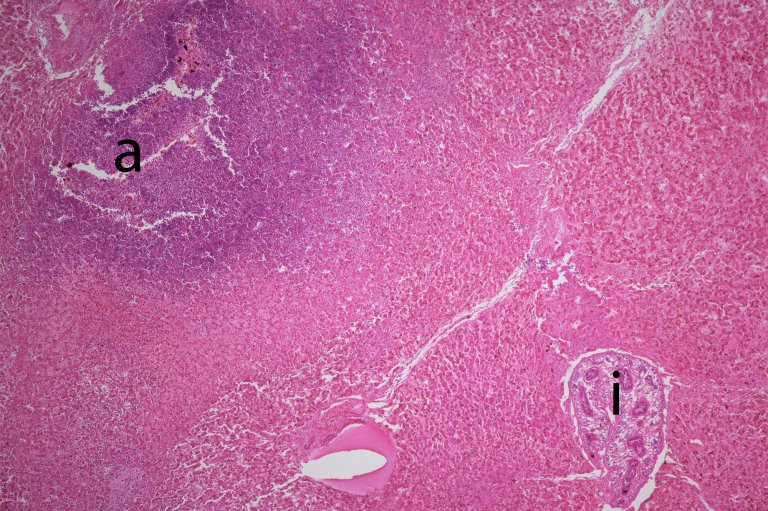

Fra andre europeiske land er det tidligere rapportert at D. dendriticum opptrer annerledes hos kamelider enn hos drøvtyggere. Når larver av den lille leverikten er kommet opp i leveren, holder den seg ikke bare til gallegangene, men enkelte kan også vandre rundt i levervevet (Bilde 2). Der utløser de en langt kraftigere reaksjon enn larver i gallegangene. Dette problemet er nå også bekreftet her i Norge av Veterinærinstituttet.

Et mikroskopbilde av en alpakkalever med en liten verkebyll og en Dicrocoelium dendriticum leverikte.

Bilde 2. Et mikroskopbilde av en alpakkalever med en liten verkebyll (merket a) og en Dicrocoelium dendriticum leverikte (merket i). Foto: Veterinærinstituttet.